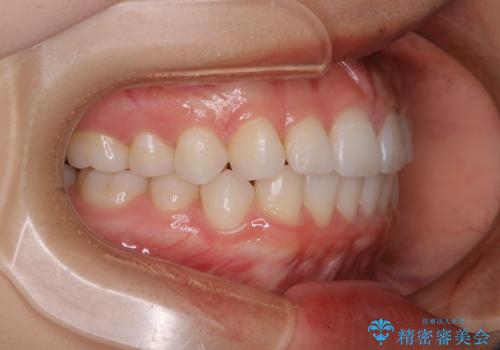

前歯のがたつきをインビザラインで治療

- 上下前歯のがたつきが気になるとの事で来院された患者様です。がたつきの程度が軽度であったため、インビザラインライトにて治療をおこないました。

がたつきの程度が軽度であったことと、インビザラインを正しく装着して頂けたことで短期間で治療終了することが出来ました。